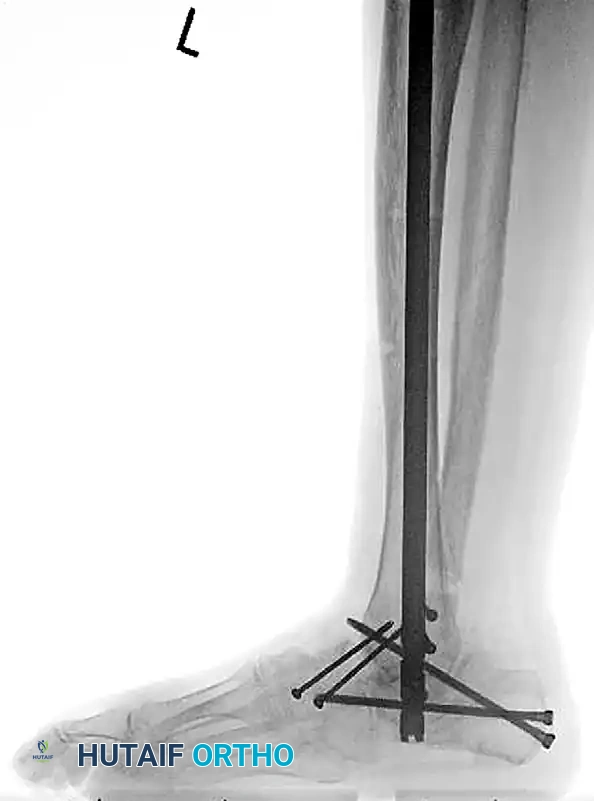

Tibiotalocalcaneal (TTC) Arthrodesis

When the ankle joint is unsalvageable due to severe Charcot destruction, realignment and extended fusion are required. A TTC arthrodesis utilizing a retrograde intramedullary nail provides a load-sharing construct that is biomechanically superior in the neuropathic patient.

Surgical Steps for TTC Nailing:

1. Preparation: The articular cartilage of the tibiotalar and subtalar joints is aggressively debrided down to bleeding subchondral bone.

2. Alignment: The foot is positioned in neutral dorsiflexion, 5 degrees of valgus, and 10 degrees of external rotation.

3. Implantation: A rigid retrograde intramedullary nail is introduced through the plantar aspect of the calcaneus, traversing the talus and into the tibial canal. Multiple locking screws are placed to secure the construct.

Image

FIGURE 85-20 A and B: Severe Charcot arthropathy of the ankle with profound deformity and joint destruction.

FIGURE 85-20 C and D: Postoperative radiographs following successful tibiotalocalcaneal (TTC) arthrodesis with a rigid retrograde intramedullary nail, restoring a plantigrade alignment.